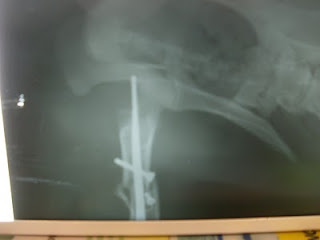

Foi-lhe feito um RX para ver o estado da sua pata, estava partida em dois, conforme se pode ver no primeiro RX. Foi submetida a uma cirurgia.

A pobre menina tem também chumbo antigo na pata, como se pode ver no último RX, mas em princípio não se vai mexer.

Raio X antes da cirurgia

Raio X depois da cirurgia